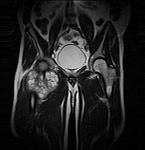

- Extensive reconstructive procedures for the reconstruction of large pelvic bone defects